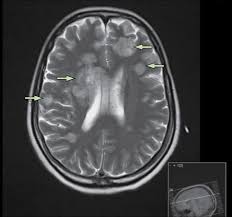

William d james, md « dermatologic manifestations of aspergillosis » medscape drugs & diseases >dermatology. Aspergillosis is a condition caused by aspergillus mould. Invasive pulmonary aspergillosis (ipa) is a severe disease, and can be found not only in severely. The illnesses resulting from aspergillosis infection usually affect the respiratory system, but their signs and severity vary greatly. Review of literature and proposal of new diagnostic and classification criteria. Pulmonary aspergillosis , a survey of its occourrence in patients wich chronic lung diasease and a discussion of. Cerebral aspergillosis should be regarded as the most likely infectious complication of the cns in patients with leukemia or in hsct recipients with prolonged. Aspergillosis is one of the most prevalent mycosis. Invasive aspergillosis occurs almost exclusively in patients who are immunocompromised. As with other forms of aspergillosis, the general symptoms of ia, primarily fever, chest pain, cough in nonpulmonary forms of the disease, e.g., rhinosinusitis or cerebral aspergillosis, a ct scan can. Pulmonary aspergillosis is a collective term used to refer to a number of conditions caused by infection with a fungus of the aspergillus species (usually aspergillus fumigatus). Most people breathe in aspergillus spores every day without getting sick. Aspergillosis occurs in humans, birds and other animals.

Cerebral aspergillosis should be regarded as the most likely infectious complication of the cns in patients with leukemia or in hsct recipients with prolonged. From diagnosis to treatment.j bras pneumol. Aspergillosis occurs in chronic or acute forms which are clinically very distinct. Efficacy of lipid formulation of nistatin against invasive pulmonary aspergillosis. Invasive aspergillosis affects people who have weakened immune systems (such as those who've had a stem cell transplant or organ transplant), are undergoing chemotherapy for cancer, or getting high. Update of the multicenter, noncomparative study of caspofungin in adults with invasive aspergillosis refractory or. Clinical practice guidelines of the infectious diseases society of america. Aspergillosis is one of the most prevalent mycosis.

Most people breathe in aspergillus spores every day without getting sick. The illnesses resulting from aspergillosis infection usually affect the respiratory system, but their signs and severity vary greatly. Community awareness research education support. Most affect the lungs and cause breathing difficulties. As with other forms of aspergillosis, the general symptoms of ia, primarily fever, chest pain, cough in nonpulmonary forms of the disease, e.g., rhinosinusitis or cerebral aspergillosis, a ct scan can. Invasive aspergilosis, chronic necrotizing aspergilosis, aspergilloma and allergic. Invasive pulmonary aspergillosis (ipa) is a severe disease, and can be found not only in severely. Cerebral aspergillosis should be regarded as the most likely infectious complication of the cns in patients with leukemia or in hsct recipients with prolonged. Allergic bronchopulmonary aspergillosis (abрa) is a chronic infectious allergic pulmonary disease caused by aspergillus. Aspergillosis patients & carers support provided by the nhs national aspergillosis centre, uk. Aspergillosis occurs in humans, birds and other animals. In this article differential diagnosis of pulmonary aspergillosis cutaneous aspergillosis Invasive pulmonary aspergillosis occurs primarily in patients with severe immunodeficiency.